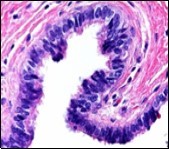

Typically, cutaneous ciliated cyst is a simple cyst which demonstrates a layering of pseudostratified ciliated columnar epithelium recapitulating conventional epithelial lining of the fallopian tube. As the cutaneous ciliated cyst demonstrates a morphological similarity to the fallopian tube lining epithelium, a Mullerian origin is indicated. Gross examination of cutaneous ciliated cyst depicts a solitary, mobile, non-tender, fluctuant, firm or soft to cystic lump with a fibrous wall and abundant amount of circumscribing adipose tissue. Cutaneous ciliated cysts are of a variable dimension. Cut surface usually displays a unilocular cyst impacted with clear, serous fluid, an attenuated smooth, greyish/ white cyst wall incorporated with incomplete septa traversing the cyst 6, 7.

Morphological analysis preponderantly demonstrates a solitary, uni-locular or multi-locular cyst of Mullerian origin with an epithelial lining recapitulating the epithelium of fallopian tube.

Cutaneous ciliated cyst is layered with a singular layer of ciliated epithelial cells which are chiefly constituted by cuboidal to columnar epithelium, traversed by partially configured fibrous tissue septa with an admixture of randomly dispersed, intraluminal papillary projections akin to those cogitated in the fallopian tube. Superimposed epithelium is inundated with well vascularized, parallel bundles of collagen although smooth muscle is absent 7, 8.

Cystic structures cogitated within deep dermal or subcutaneous tissue can be impacted with haemorrhagic fluid. Cyst lining is smooth, regular and is essentially composed of a singular layer of columnar epithelium with focally pseudostratified columnar epithelium, a circumscription of loosely configured, well vascularized, fibroconnective or fibrocollagenous tissue and an absence of inflammatory infiltrate.

Alternatively, cutaneous ciliated cyst can be lined by non ciliated cuboidal or columnar epithelium with intermingled intercalated, dark or round peg cells. Foci of squamous metaplasia can be occasionally exemplified in the adherent epithelium whereas mucinous cells or apocrine-like features are exceptional 6, 8. Figure 1, Figure 2, Figure 3, Figure 4, Figure 5, Figure 6, Figure 7, Figure 8, Figure 9, Figure 10, Figure 11, Figure 12. 11, 12, 13, 14, 15, 16, 17, 18, 19.

Figure 1.Ciliated cutaneous cyst lined by pseudostratified ciliated columnar epithelium and a supporting fibro-connective tissue stroma 11.